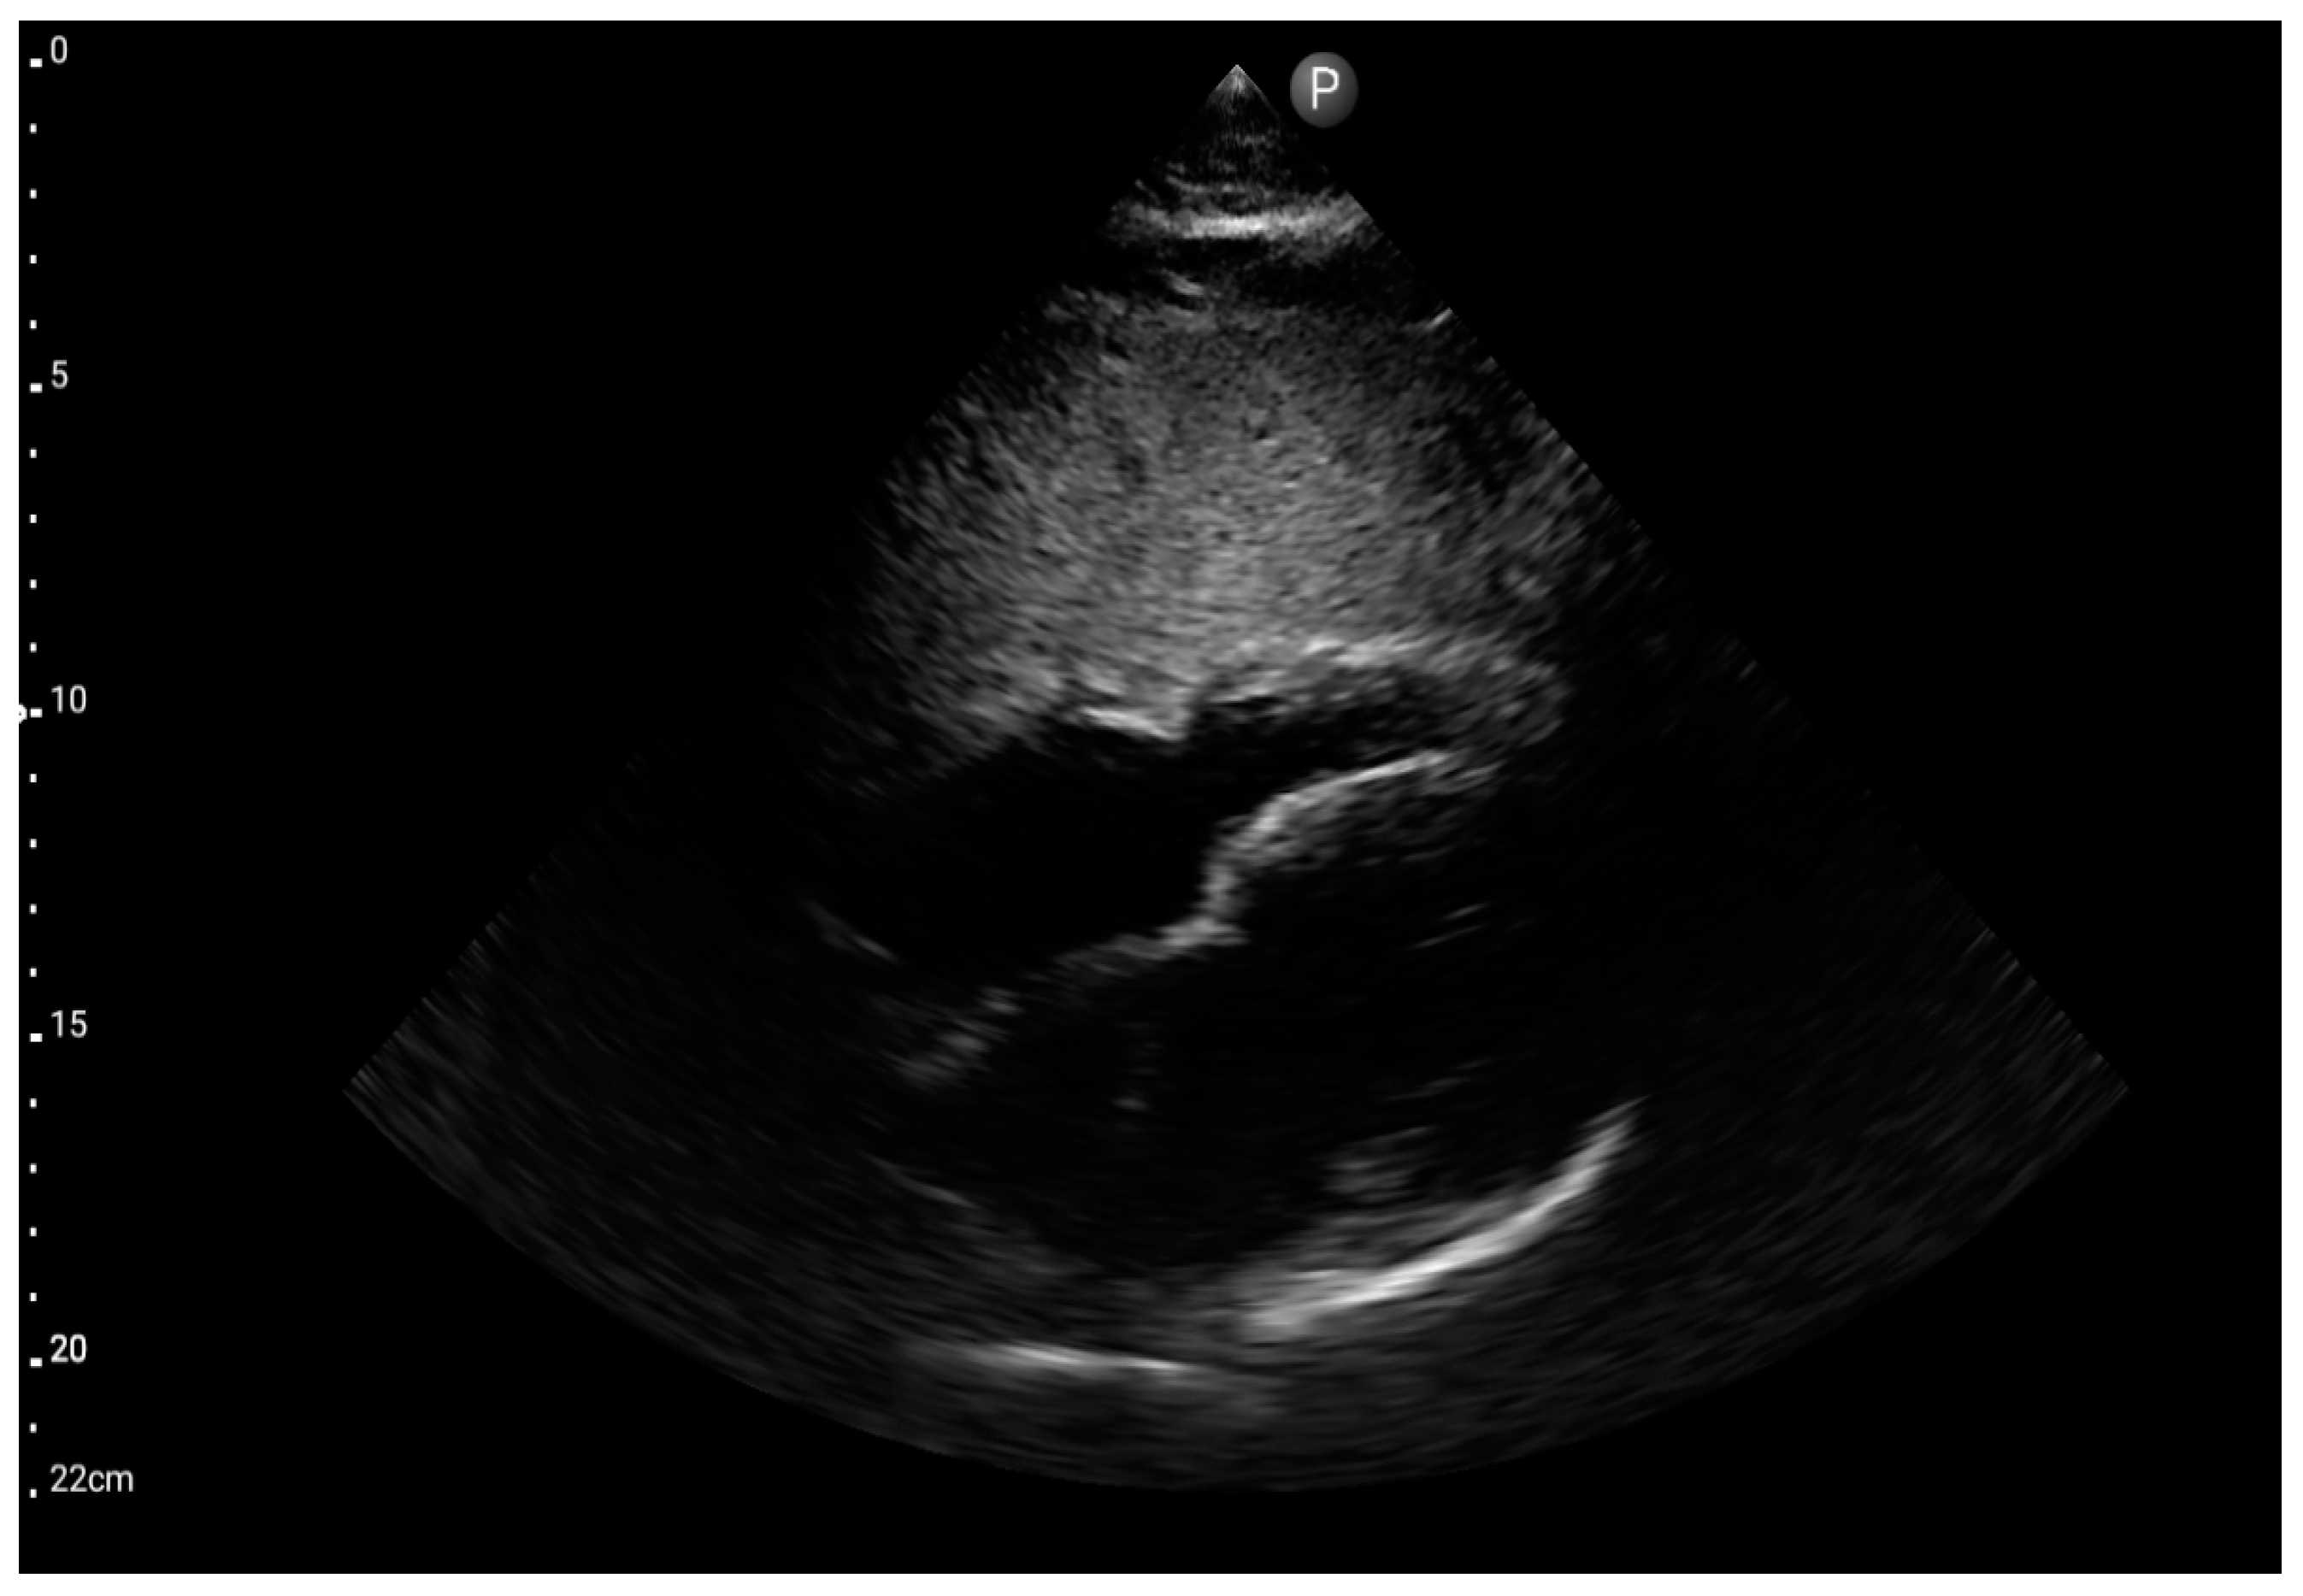

Figure 7.

Sector probe; view: subcostal four-chamber (FATE protocol) (source: author’s material—DK).